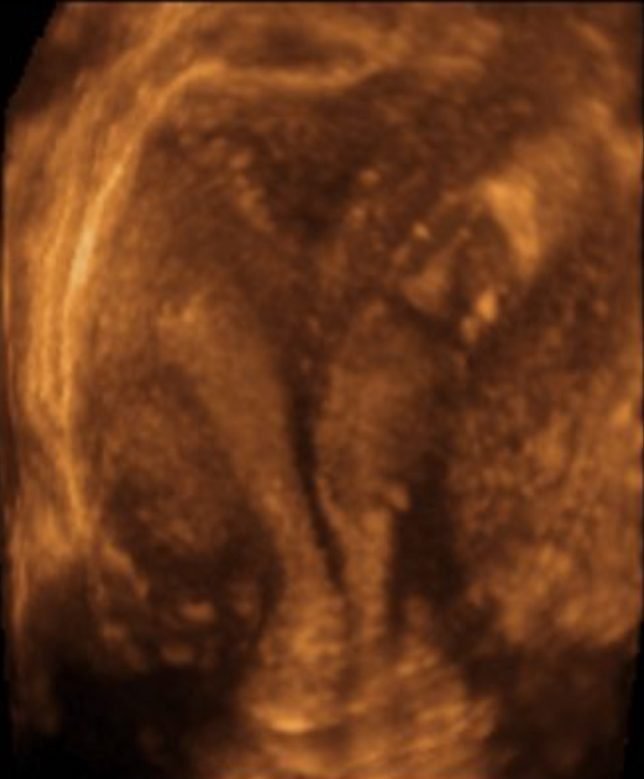

2. Beware of the false positives.

One of the most common reasons for an HSG today is to check for tubal patency. Office-based saline-infusion sonography (SIS), especially when combined with a 3D reconstruction, is very effective for providing views of the uterus and cavity and this study (so-called virtual hysteroscopy) has essentially replaced HSG for exploring uterine malformations, Asherman Syndrome, etc.

3. Low pressure or high?

There are two somewhat different goals of HSG: to test the patency of the fallopian tubes and to visualize the contours of the cavity. Higher pressure of the contrast medium helps distend the walls of the uterus but is also more likely to cause tubal or cornual spasm, leading to a false positive result. So, a low pressure technique is more effective if the primary aim is to test the patency of the tubes, which is the most common objective of HSG. Inject the contrast medium at a slow and steady pressure and you shouldn’t need more than 2 or maybe 3 ml for the whole study. If the patient reports significant cramping, you are probably using a too much pressure (and that cramping may be associated with tubal spasm).

Sometimes due to the acuteness of the uterocervical angle, the flexible catheter cannot pass easily into the endometrial cavity. Other times, the views of the cavity are incomplete because the tip of the catheter (and the balloon) are situated in the cornua and the contrast doesn’t distend the rest of the cavity well. Or, sometimes, the cavity won’t distend well because the contrast is leaking of the cervix.

In each of these cases, try this: place the catheter balloon in the cervix rather than the endometrial cavity, near the internal os, and inflate it. This will put the tip of the catheter in the lower uterine segment and the inflated balloon will occlude the cervical canal enough to force the contrast material upwards. This usually works and can make using a painful tenaculum unnecessary (either to pull on and straighten out the uterocervical angle or to try to occlude the cervical canal).